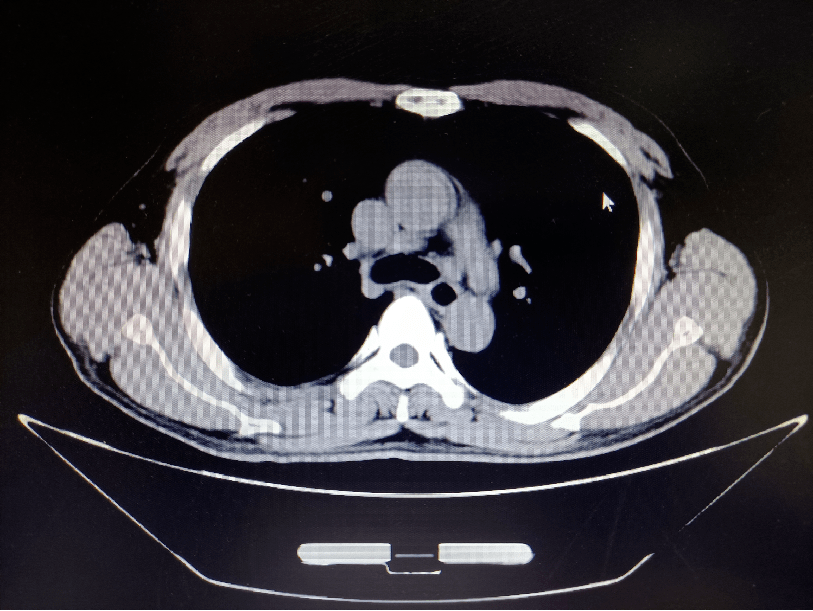

胸部ct:食管中上段部分管壁不规则增厚,考虑食管癌;邻近周围多发肿大

ct检查发现食管癌病灶较大7x5cm,已压迫气管分叉及左右主支气管,尤其